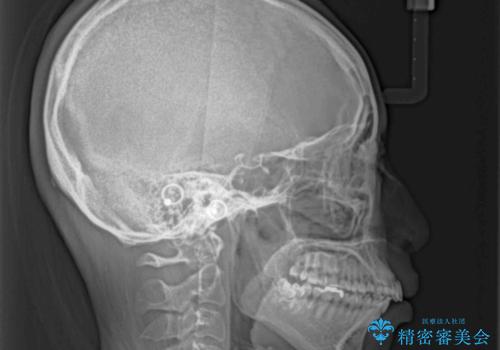

- くちばしのような前歯の突出感を気にして来院された患者様です。

上下左右第一小臼歯4本を抜歯して、積極的に口元を引っ込めるよう、ワイヤー装置にて矯正治療を行うこととしました。